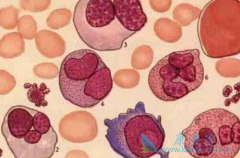

骨髓瘤症状 有哪些?早期骨髓瘤能治好吗?在骨髓瘤的发病人群中,多是中年和晚年患者。我们平时说的骨髓瘤,多属于多发性骨髓瘤,它的发病率是比较高的。恶性骨髓瘤在人的椎体,肋骨,胸骨,颅骨和骨盆为其好发部位。说到早期骨髓瘤的治疗,就不得不来说一 ...

纤维化前 骨髓纤维化 (pre-PMF)是原发性骨髓纤维化(PMF)的早期阶段,属于一种具有惰性临床表现与良好预后的骨髓增殖性肿瘤(MPN)。pre-PMF临床表现多样,可表现为孤立的血小板增多症,酷似原发性血小板增多症(ET),也可表现为高危PMF的症状。2016年修订版 ...

多发性 骨髓瘤能活多久 ?没有确切的答案,这跟诸多因素有关,还要根据患者的病情发展来判断。早期骨髓瘤常常有疼痛症状,而这种疼痛的特点是持续时间长,并且进行性加剧,随着疾病的发展,有的病人到最后痛不欲生。所以这种情况发生要及时治疗。骨髓瘤患 ...

骨髓纤维化( MF)是一种慢性骨髓增殖性肿瘤。约90%的MF患者有JAK2V617F突变或CALR或MPL基因突变。目前已获批用于治疗MF的唯一靶向药物芦可替尼/ 鲁索替尼 对大部分患者有缩小脾脏、改善全身症状、逆转或稳定MF的疗效, 而不论患者是否有JAK2V617F突变。 ...